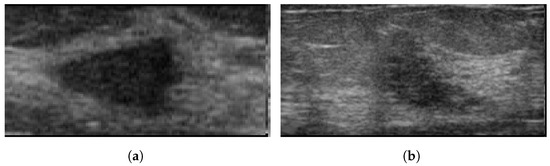

4.3. Ultrasonography

- Becker, A.S.; Mueller, M.; Stoffel, E.; Marcon, M.; Ghafoor, S.; Boss, A. Classification of breast cancer in ultrasound imaging using a generic deep learning analysis software: A pilot study. Br. J. Radiol. 2018, 91, 20170576. [Google Scholar] [CrossRef]

- Qian, X.; Pei, J.; Zheng, H.; Xie, X.; Yan, L.; Zhang, H.; Han, C.; Gao, X.; Zhang, H.; Zheng, W.; et al. Prospective assessment of breast cancer risk from multimodal multiview ultrasound images via clinically applicable deep learning. Nat. Biomed. Eng. 2021, 5, 522–532. [Google Scholar] [CrossRef]

- Almajalid, R.; Shan, J.; Du, Y.; Zhang, M. Development of a Deep-Learning-Based Method for Breast Ultrasound Image Segmentation. In Proceedings of the 2018 17th IEEE International Conference on Machine Learning and Applications (ICMLA), Orlando, FL, USA, 17–20 December 2018; pp. 1103–1108. [Google Scholar]

- Han, S.; Kang, H.K.; Jeong, J.Y.; Park, M.H.; Kim, W.; Bang, W.C.; Seong, Y.K. A deep learning framework for supporting the classification of breast lesions in ultrasound images. Phys. Med. Biol. 2017, 62, 7714. [Google Scholar] [CrossRef]

- Yap, M.H.; Pons, G.; Martí, J.; Ganau, S.; Sentis, M.; Zwiggelaar, R.; Davison, A.K.; Marti, R. Automated breast ultrasound lesions detection using convolutional neural networks. IEEE J. Biomed. Health Inform. 2017, 22, 1218–1226. [Google Scholar] [CrossRef]

- Jabeen, K.; Khan, M.A.; Alhaisoni, M.; Tariq, U.; Zhang, Y.D.; Hamza, A.; Mickus, A.; Damaševičius, R. Breast Cancer Classification from Ultrasound Images Using Probability-Based Optimal Deep Learning Feature Fusion. Sensors 2022, 22, 807. [Google Scholar] [CrossRef]

- Tanaka, H.; Chiu, S.W.; Watanabe, T.; Kaoku, S.; Yamaguchi, T. Computer-aided diagnosis system for breast ultrasound images using deep learning. Phys. Med. Biol. 2019, 64, 235013. [Google Scholar] [CrossRef]

- Ilesanmi, A.E.; Chaumrattanakul, U.; Makhanov, S.S. A method for segmentation of tumors in breast ultrasound images using the variant enhanced deep learning. Biocybern. Biomed. Eng. 2021, 41, 802–818. [Google Scholar] [CrossRef]

- Huang, K.; Zhang, Y.; Cheng, H.; Xing, P.; Zhang, B. Semantic segmentation of breast ultrasound image with fuzzy deep learning network and breast anatomy constraints. Neurocomputing 2021, 450, 319–335. [Google Scholar] [CrossRef]

- Hijab, A.; Rushdi, M.A.; Gomaa, M.M.; Eldeib, A. Breast Cancer Classification in Ultrasound Images using Transfer Learning. In Proceedings of the 2019 Fifth International Conference on Advances in Biomedical Engineering (ICABME), Tripoli, Lebanon, 17–19 October 2019; pp. 1–4. [Google Scholar]

- Kim, J.; Kim, H.J.; Kim, C.; Lee, J.H.; Kim, K.W.; Park, Y.M.; Kim, H.W.; Ki, S.Y.; Kim, Y.M.; Kim, W.H. Weakly-supervised deep learning for ultrasound diagnosis of breast cancer. Sci. Rep. 2021, 11, 24382. [Google Scholar] [CrossRef] [PubMed]